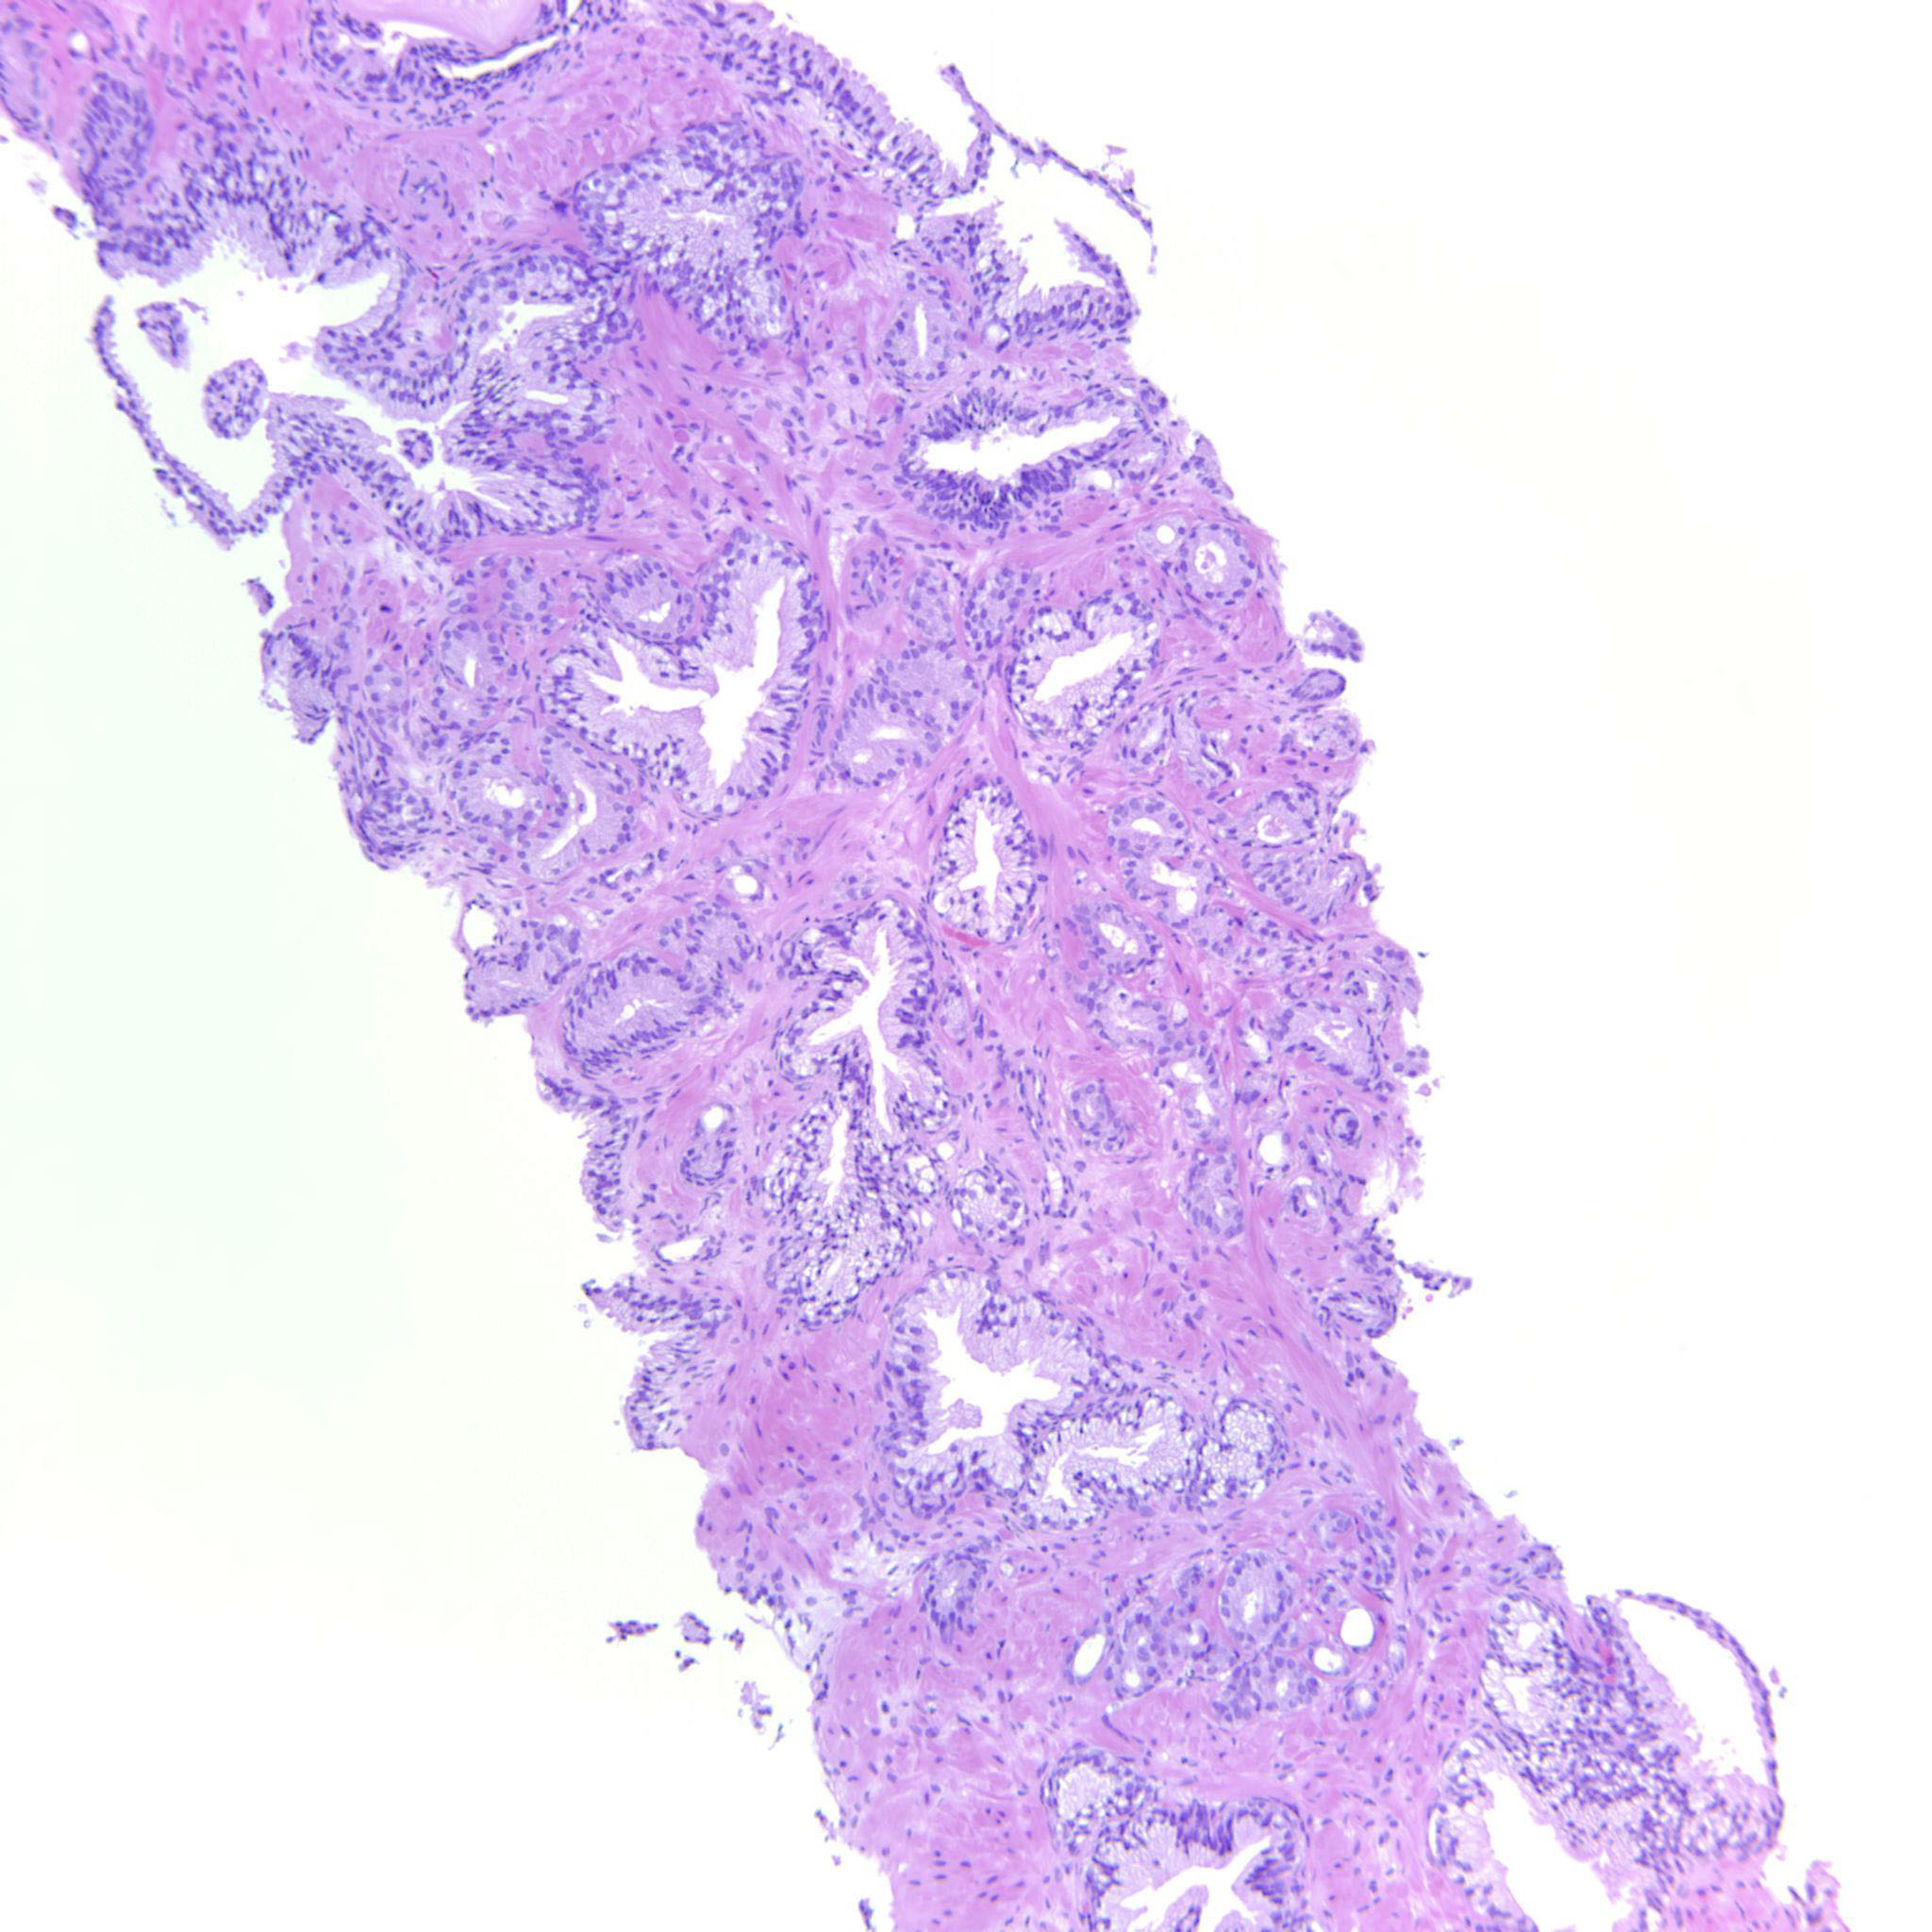

Prostate cancer grading

Case ID: 480